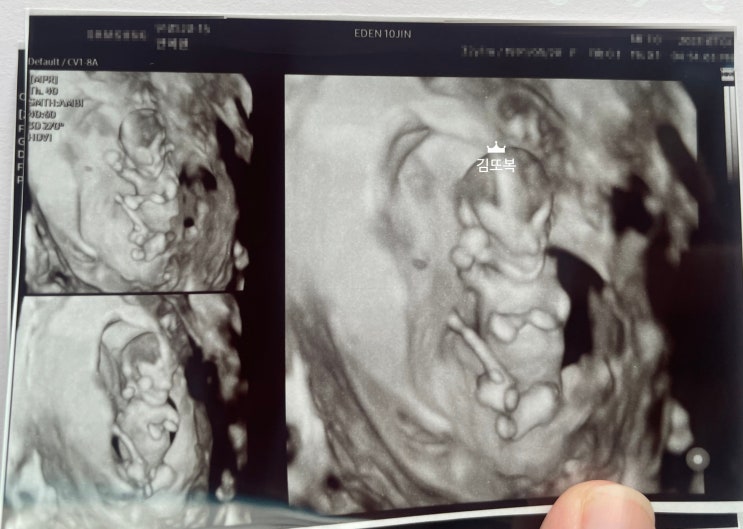

[임신일기 11주~15주] 임신 이벤트, 임신 중 출혈, 1차 기형아검사, 임신초기 끝, 임신중기 시작, 나의 일상

광주산부인과는 에덴병원(with.의사추천, 예약방법, 이용방법, 응급실 위치, 산모수첩, 세이베베)

조리원 후기는 많은데, 산부인과 후기는 안보여서 제가 다니고 있는 산부인과 에덴병원에 대해 기록해보려...